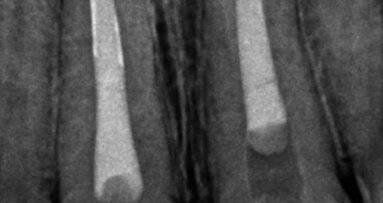

A young male patient came into the integrated dentistry clinic at Universidade Severino Sombra needing restorative treatment of tooth #21. In the clinical and radiographic examination, significant coronal destruction and satisfactory endodontic treatment were noted (Figs. 1–3).